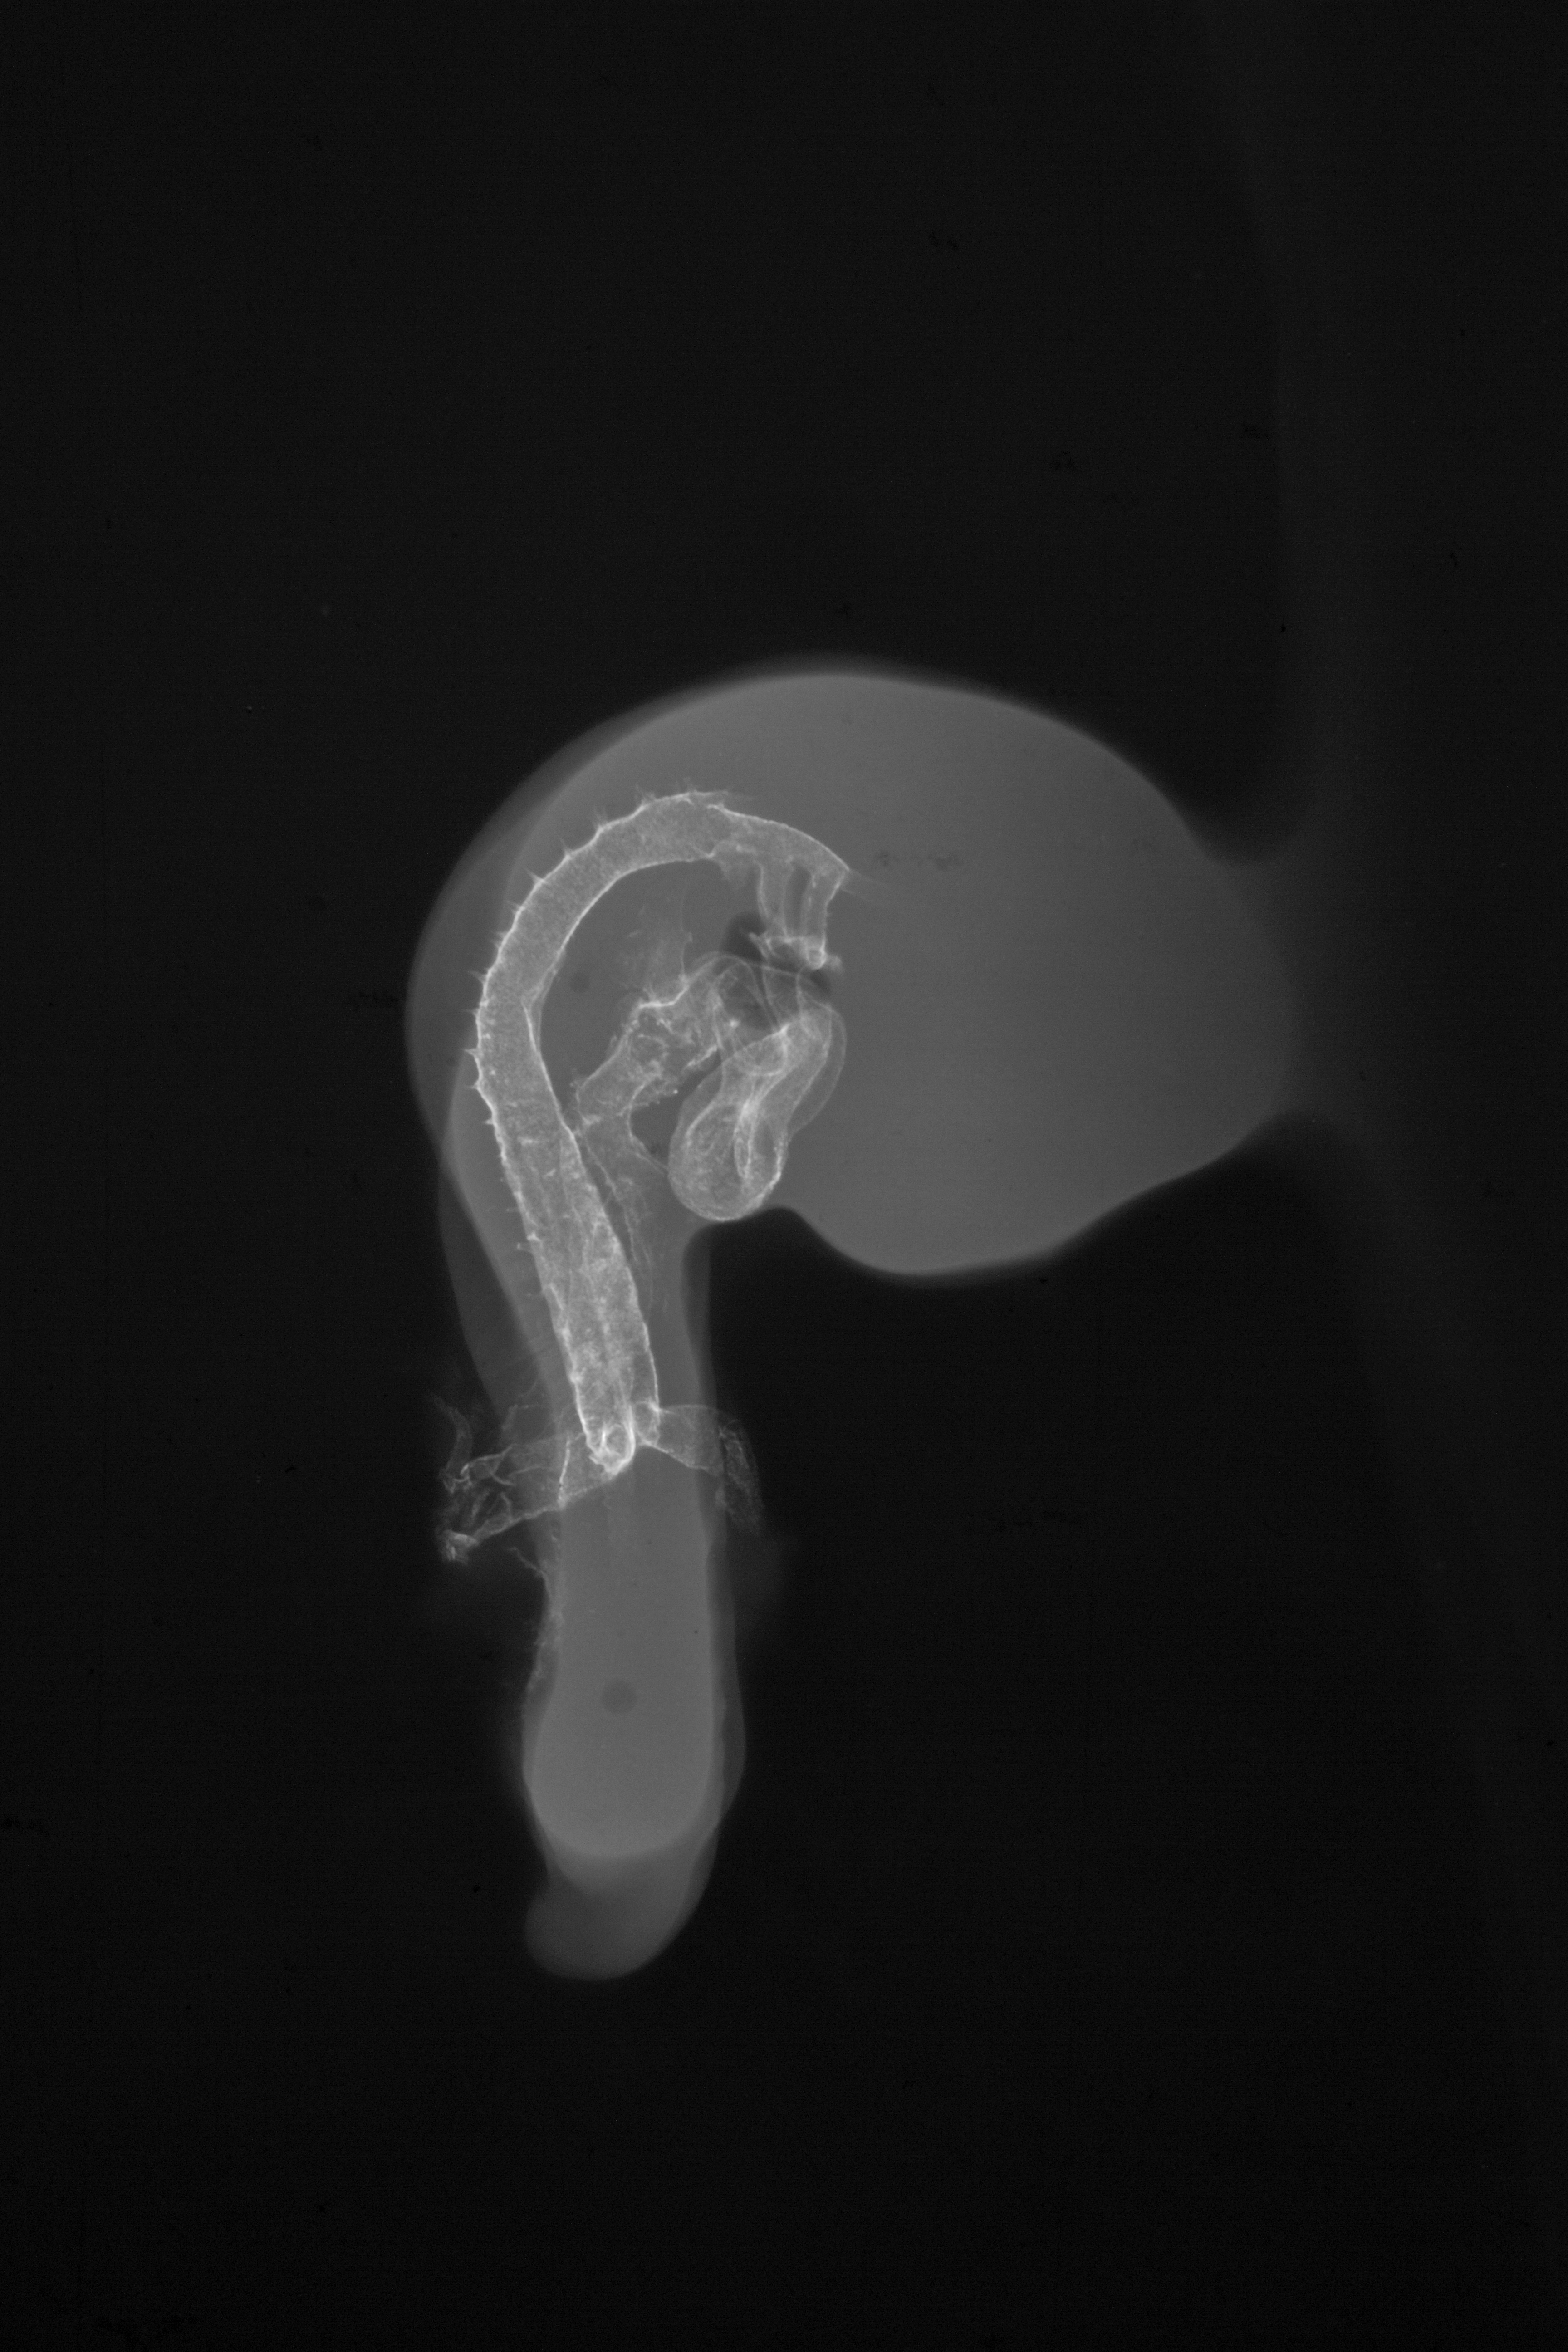

Chick Embryo Microangiography

Hamburger-Hamilton (HH) Stage 18 (approx. 3 days)

Stereo X-Ray Micrographs